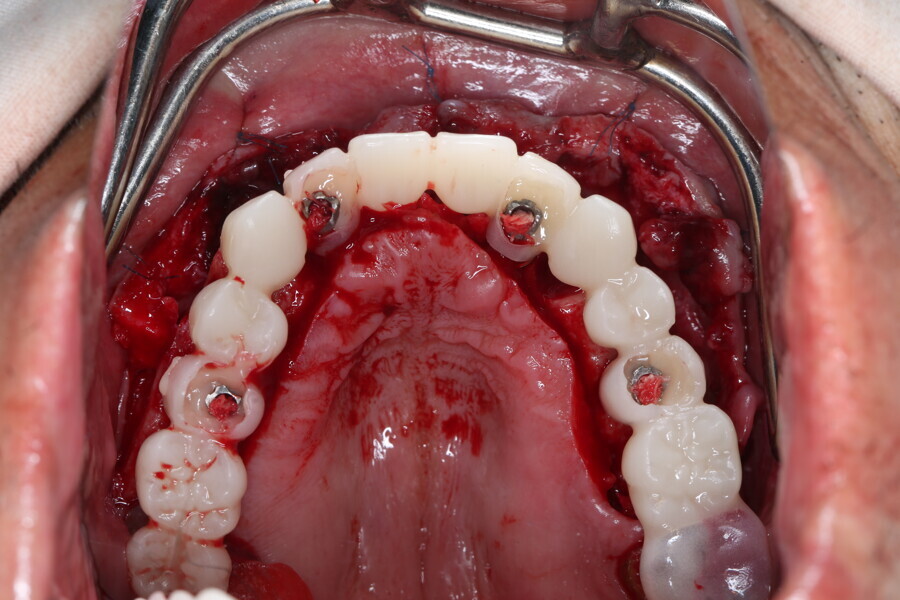

Compromised maxillary dentition treated with Straumann Pro Arch and a digital workflow